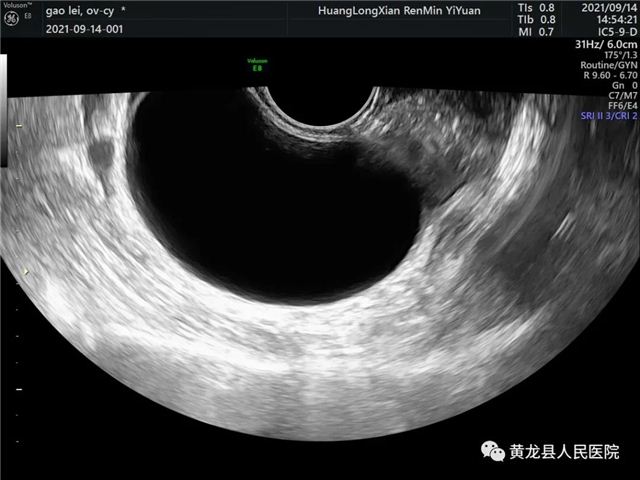

腔内卵巢囊肿超声图像

患者,34岁,12年前通过检查发现右侧卵巢囊肿,多年来未进行治疗,近日,患者来黄龙县人民医院复查,通过超声检查发现囊肿由原来的1.3×1.7cm增大到现在的6×4.8cm,卵巢囊肿标志物正常,提示卵巢良性肿瘤,考虑囊肿时间较长,且逐渐增大,建议患者手术治疗。经患者同意,做好各项术前准备,于9月14日为患者成功实施经阴道超声引导下卵巢囊肿穿刺硬化术,手术由延安大学附属医院派驻专家超声科白宝艳和妇科专家师晓艳副主任医师联合,仅十分钟左右就顺利完成手术,解决了患者12年来因疾病所受的情绪和生活困扰。此项手术属于微创手术,术后无切口、无出血、无需住院,手术结束就可以回家。目前,需要解决类似疾病患者还有很多,对于此类疾病大家要有足够的认识和警惕。

手术过程离不开B超室老师的精准定位!定位后,将穿刺针在超声引导下刺入卵巢囊肿,先将囊肿腔内液体抽吸干净,囊肿不能单纯只做穿刺,那样的话囊肿会很快复发,我们在穿刺抽吸的基础上,还需要进行囊肿的硬化治疗,今天我们用的硬化剂是聚桂醇。因为聚桂醇为醚类化合物,所以在治疗复发性卵巢囊肿方面起到了独特的微麻作用,对注射的病灶局部组织有轻微的麻醉作用,可以有效减轻患者术后局部病灶的疼痛感,可以最大限度提高患者应对卵巢囊肿清除术中的耐受性。穿刺的伤口非常小,做完穿刺局部压迫就会愈合。